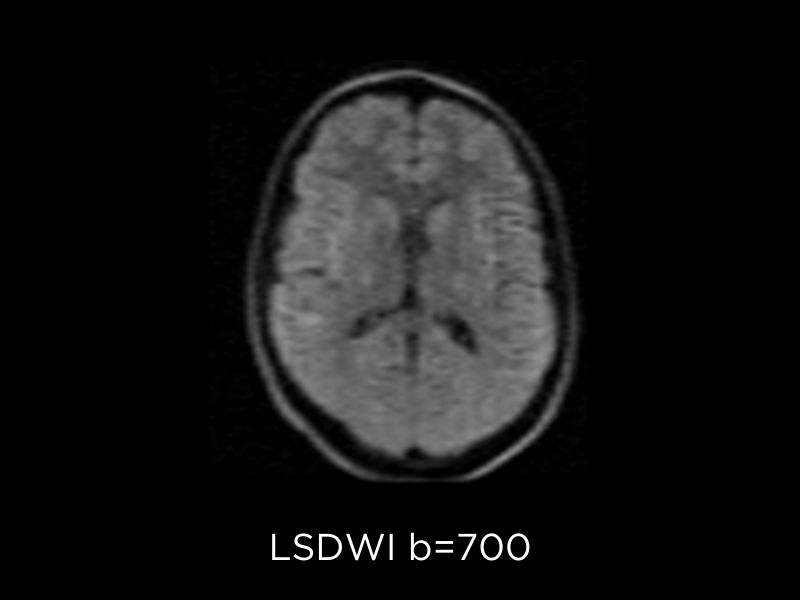

Neuroimaging clinical images

Diffusion Weighted Imaging (DWI) is a fundamental sequence to detect brain tumors, their classification and grading and monitoring. On Magnifico Open, Esaote implemented the DWI sequence with line scan technology1: this technique is based on spin echo sequences and has reduced susceptibility to static field inhomogeneities than echo planar imaging (EPI). In addition, it does not require enhanced gradient hardware and offers easy installation and reduced power consumption.

DWI provides important clinical value especially in the assessment of Cerebral Infarction and Stroke, Neoplasia, Emphysema, Toxic and Demyelinating pathologies.